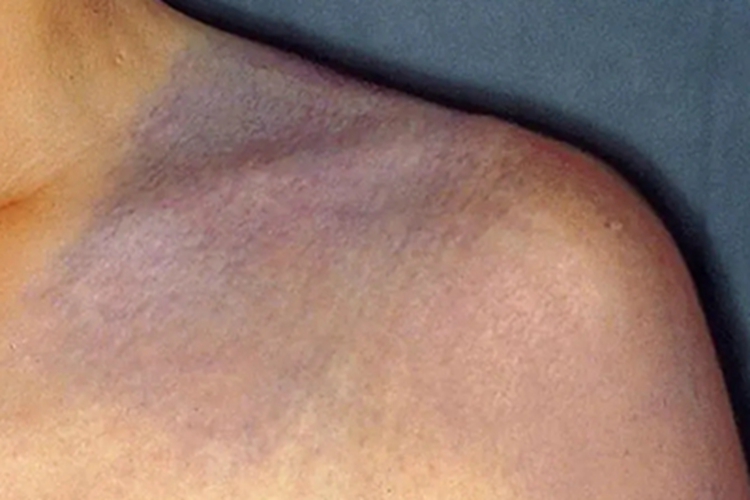

伊藤痣可导致患者的肩部出现斑样损害,颜色多呈青紫色,与周围正常皮肤界限明显。其发生多与遗传有关,可选择激光治疗。

伊藤痣皮损可发生在患者的肩部,检查见患处有斑片样损害,颜色多呈青紫色,皮损表面粗糙,与周围正常皮肤分界明显。